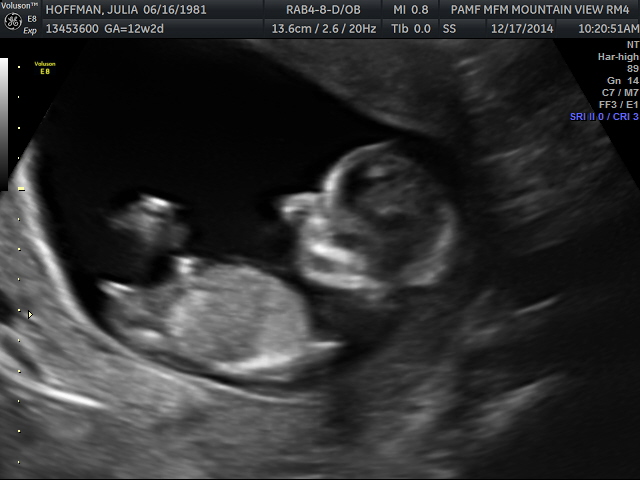

Posting for a friend. Ultrasound tech had 70% girl guess. Would love to know your thoughts!

very girly!

12w2d looks very girly x